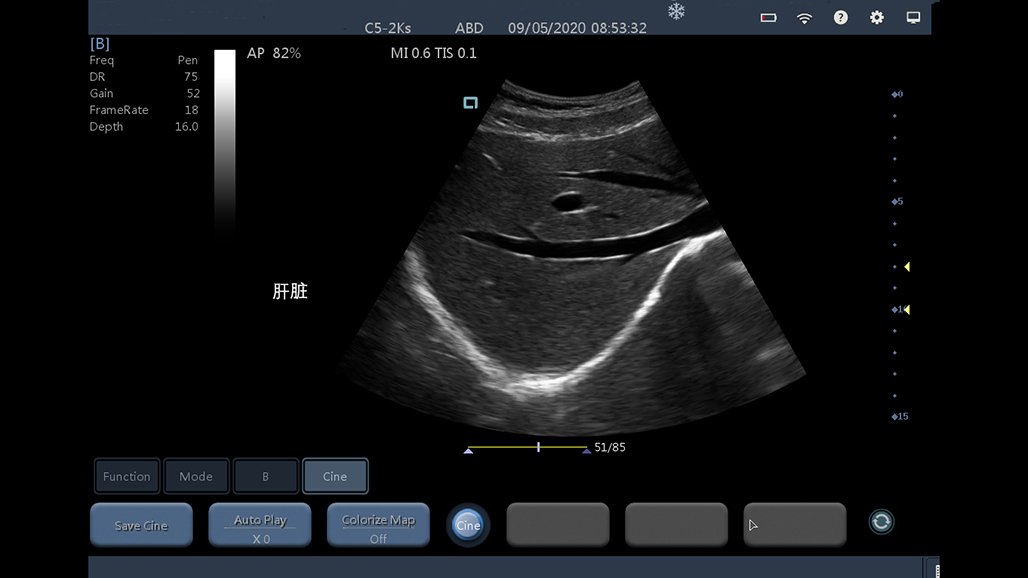

• 大凸

腹部

肾脏

妇科产科

心脏

肺等